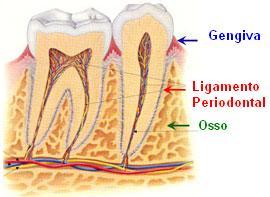

O periodonto é tudo que está em volta do dente: gengiva, ligamento (que segura o dente ao osso) e estrutura óssea. É uma região muito sensível e a qualquer agressão (as mais comuns, a placa e o tártaro) começa a se desorganizar. A gengiva inflama (gengivite) e sangra começando a se afastar do que a agride, se movendo e expondo a raiz do dente. O osso, para não aparecer também foge da agressão, diminuindo a fixação do dente e o deixando com mobilidade.

Além disso uma sensibilidade grande passa a ocorrer, pois a raiz de nosso dente é o lugar mais sensível a estímulos (frio, quente, escovação, doce…).